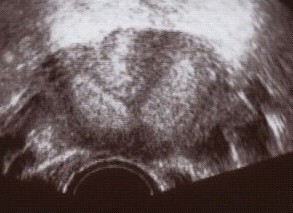

שני מומי הרחם הנפוצים ביותר בנשים עם הפלות חוזרות הם הרחם עם המחיצה (Septated uterus) המהוים כ- 35% מן המומים ורחם דו קרני - (Bicornuate uterus) המהוים כ– 40% מן המומים.

רחם עם מחיצה הוא רחם שבחללו קיימת מחיצה המחלקת אותו לשני חלקים (או קרניים). גודלה של המחיצה יכול לנוע ממחיצה חלקית ועד למחיצה מלאה. המחיצה, שניתן לדמיינה כמעין עמוד היורד מתקרתו של אולם, בנויה מרקמה השונה בהרכבה משריר הרחם ואשר אספקת הדם אליה אינה עשירה כאספקת הדם לשריר הרחם ולכן, עובר אשר נקלט ומשתרש באיזור המחיצה סיכויו לשרוד קטנים יותר. הטיפול במקרים אלה הוא הסרת המחיצה על מנת לשפר את סיכויי העובר להשתרש רק באיזורים בהם צפויה השתרשות אופטימלית יותר.

רחם דו קרני הוא רחם אשר מורכב למעשה משני רחמים וכל רחם כזה הוא "קרן". בשלב מוקדם מאד בחיים העובריים הרחם הנורמלי נוצר מהתאחדות שני צינורות שריריים הנקראים צינורות מילריאניים (Mullerian ducts). בנקודת המפגש שלהם נספג הדופן המשותף שלהם במלואו וכך נוצר חלל רחם אחד. ברחם דו קרני, תהליך זה אינו מתקיים, בדרגות שונות, ונוצר רחם עם שתי קרניים כמו אוזני ארנב. לרחם כזה גם כן שני חללים כמו ברחם המחיצתי אבל החלק האמצעי בנוי מרקמת שריר תקינה. מנגנון ההפלה ברחמים כאלה אינו על רקע יכולת השתרשות לקויה, כמו ברחם מחיצתי, אלא במנגנון אחר שאינו ברור די צורכו וקשור יותר לאי ספיקה של צואר הרחם. ברחם כזה ההפלות מאוחרות יותר ומתחילות בהתרחבות צואר הרחם בפקיעת קרומים ובירידת מים. הפרוגנוזה (הסיכוי להריון תקין) במקרה של רחם דו קרני טובה מזו של רחם עם מחיצה ואינה דורשת תיקון כירורגי כפי שהיה בשנים עברו.

הכלי הזמין ביותר לאבחון מומי רחם או שרירנים הוא האולטרה-סאונד. בעזרתו ניתן להעריך את מבנה הרחם, האם הוא דו קרני או מחיצתי והאם ישנם שרירנים המעוותים בצורה משמעותית את חלל הרחם. אולטרה-סאונד תלת ממדי נותן כלי נוסף להערכה זו.